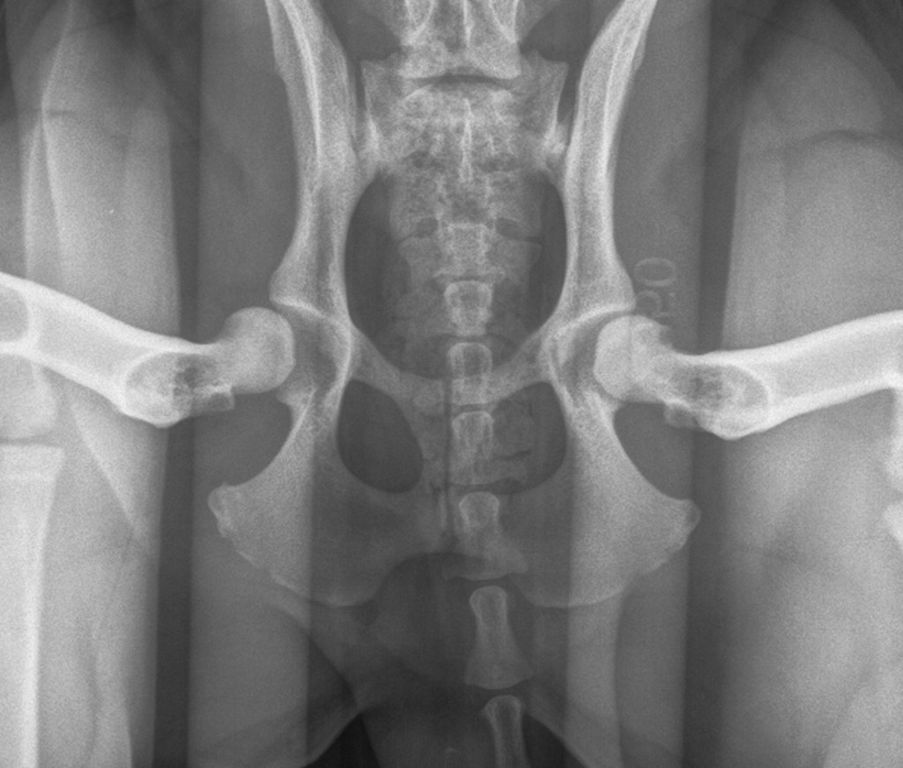

Ad oggi solo 2 medici veterinari in Italia sono abilitati ad effettuare questa metodica. Si effettuano 3 distinte radiografie (vedi foto) con il cane in sedazione.

La lettura delle radiografie viene effettuata esclusivamente dal centro di lettura PennHIP dell’Università della Pennsylvania.